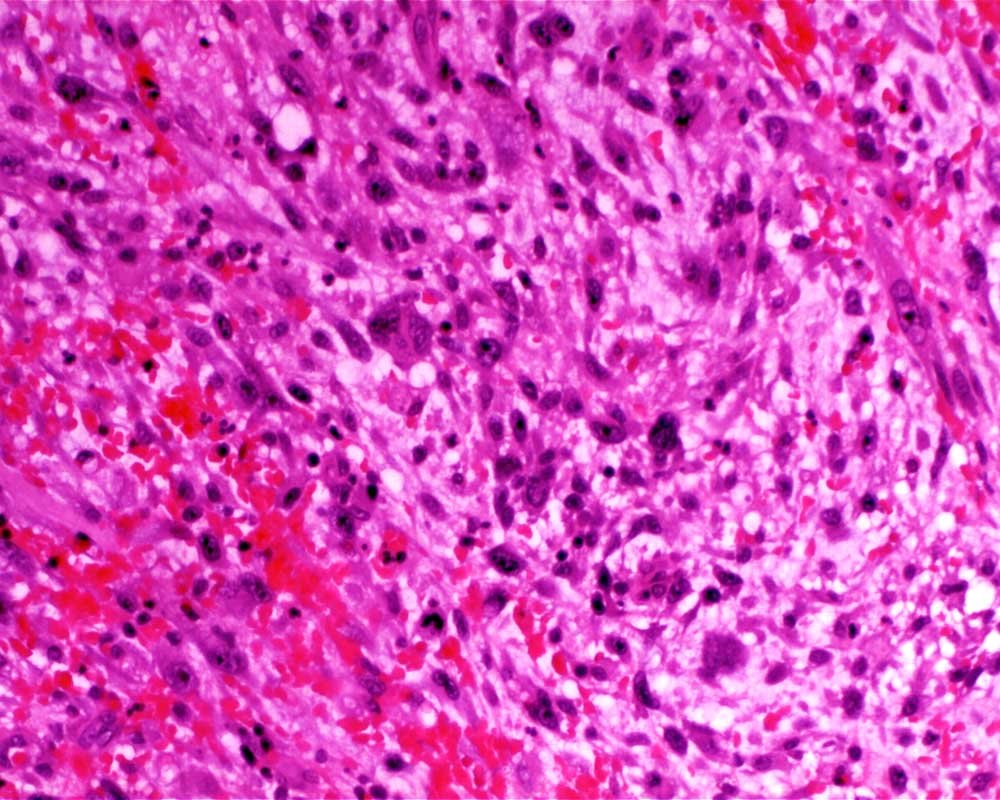

Case: LegMass

Final Diagnosis: